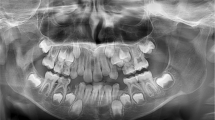

In this retrospective, blind, cross-sectional study, 160 dental panoramic radiographs (DPTs) were selected from 420 DPTs from healthy children aged between three and 10 years old from the archived medical files of patients attending Minia University Dental Hospital (MUDH) and evaluated to estimate dental ages.

DPT and personal information related to the CA of each subject, such as the DOB and DOR, were collected from the existing records. Each DPT was assigned a code, scanned at a resolution of 300 dpi in gray-scale format, and stored as a JPEG image with dimensions of 2440 × 1280 pixels (Epson scanner 1000XL, Epson Inc., USA). The CAs of the participants were calculated by subtracting the DOB from the DOR and were recorded as years with two decimal places.17

The DA was calculated using Demirjian’s method. All of the teeth in the lower left jaw (with the exception of the third molar) were assessed.18 The DA was calculated according to the tables proposed by Demirjian et al.4 When a tooth on one side was missing or difficult to read, the contralateral tooth was assessed. A Microsoft Excel 2010 (Microsoft Corp., USA) database was used for data entry.